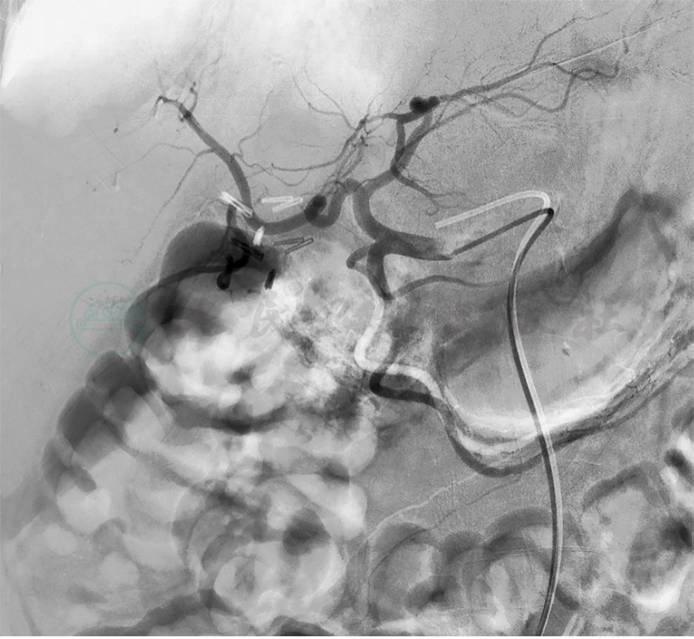

考虑贫血严重,全身情况较差,入院后给予补液扩容改善贫血等支持治疗,血红蛋白纠正至74g/L。第3天:患者排黑便数次,量1 000mL左右,急查血红蛋白53g/L。初步诊断急性消化道出血,首选早期胃镜检查。数字减影血管造影(digital subtraction angiography,DSA)与CTA检查同样具有较好的诊断价值,结合该患者具有十二指肠乳头占位,肿瘤合并出血的可能性较大。因此,首先选择了急诊胃镜检查,发现十二指肠乳头处有隆起占位性病变,局部黏膜粗糙,并有持续少量渗血(图4)。为控制出血,我们继而选择了数字减影血管造影(DSA)栓塞胃十二指肠动脉(gastroduodenal artery,GDA)止血(图5)。DSA术后1周,患者出血停止,血红蛋白逐渐上升至71g/L。

图5 DSA-GDA栓塞止血

3.急性消化道出血的治疗

由于内镜下无法对乳头内的渗血作处理,急诊手术又存在非常大的风险,因此选择DSA-GDA栓塞术,尽管在DSA下并未见到造影剂外溢。但疗效说明一切,栓塞治疗后患者的血色素逐渐上升,出血停止。换一个角度,如果之前医师先选择了DSA检查,但未见有造影剂外溢,会给后续的治疗选择造成非常大的困扰。